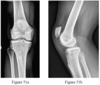

- Figures 11a through 11c are the radiograph and MR images of a 10-year-old boy who has had 4 weeks of lateral knee pain that began while he was playing soccer. The pain is only present with physical activity, and he does not have any catching symptoms. An examination reveals minimal symptoms with provocative maneuvers and no effusion. What is the most appropriate initial treatment?

- Activity modification and decreased weight bearing

- Arthroscopic removal of the fragment

- Arthroscopic retrograde drilling

- Arthroscopic open reduction and internal fixation

- Observation with no change in athletic activity

- Activity modification and decreased weight bearing